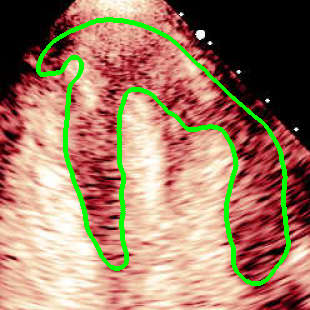

For variations caused by low quality images such as those of low resolution or significant artifacts, however, the unique ground truth may not be available. Take the myocardial segmentation task of Myocardial Contrast Echocardiography (MCE) as an example. An inter-observer experiment was conducted among five experienced cardiologists, and Fig. 1(a)(b) visualize the annotations of two images from three of these cardiologists. It can be seen that the labels by different cardiologists vary significantly, especially in locations where the intensity information of myocardium is very similar to the background. Table 1 shows the average Dice of the annotation of each cardiologist, using one of the others’ as the ground truth, over 180 images. We can observe that none of the Dice is above 0.9, some even under 0.8, confirming significant variations among the annotations. In this case, as the variations are caused by the image quality, even these cardiologists cannot tell which annotation is better than others, and a majority vote for ground truth would not make sense sometimes as can be seen in Fig. 1(c)(d). For this reason, we cannot obtain a unique ground truth in the evaluation process and the traditional metrics such as Dice and IoU cannot be used.